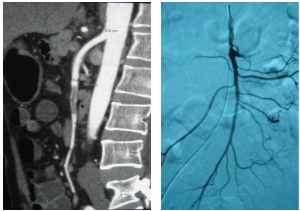

25岁,肥胖男性,体重125kg,主诉:腹痛10余天,加重2天、便血1天。

术中及术后标本,术后查因:诊断为高同型半胱氨酸血症 (易栓症),积极术后抗凝、随访中。

★ 案例七

73岁,德国男性,肥胖体型,既往有糖尿病、冠心病、高血压,主诉:腹痛1周,加重2天。切除坏死小肠380cm,闯过感染休克关、MOF关、切口裂开再手术关、新冠肺炎等关,乘德国医疗转运飞机回国。